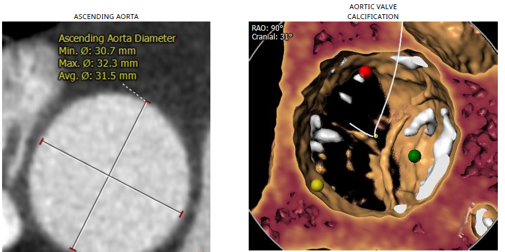

患者资料:84岁女性,既往有高血压、糖尿病、冠心病病史,5年前曾行PCI手术,此次入院诊断为主动脉瓣重度狭窄伴关闭不全,瓣环内径18.5mm,AV Vmax 3.79m/s,LVOT 23.7mm,有效瓣口面积0.6m²。

考虑到患者高龄,合并多种病症,且为PCI后再行TAVR,手术存在较高的血管并发症风险,对TAVR瓣膜器械的选择提出了较高要求。经多专家、多学科讨论,罗建方、谭冠昶教授最终选择使用Evolut PRO+开展此台TAVR手术,以为患者提供最佳的手术体验和更好的手术保障。